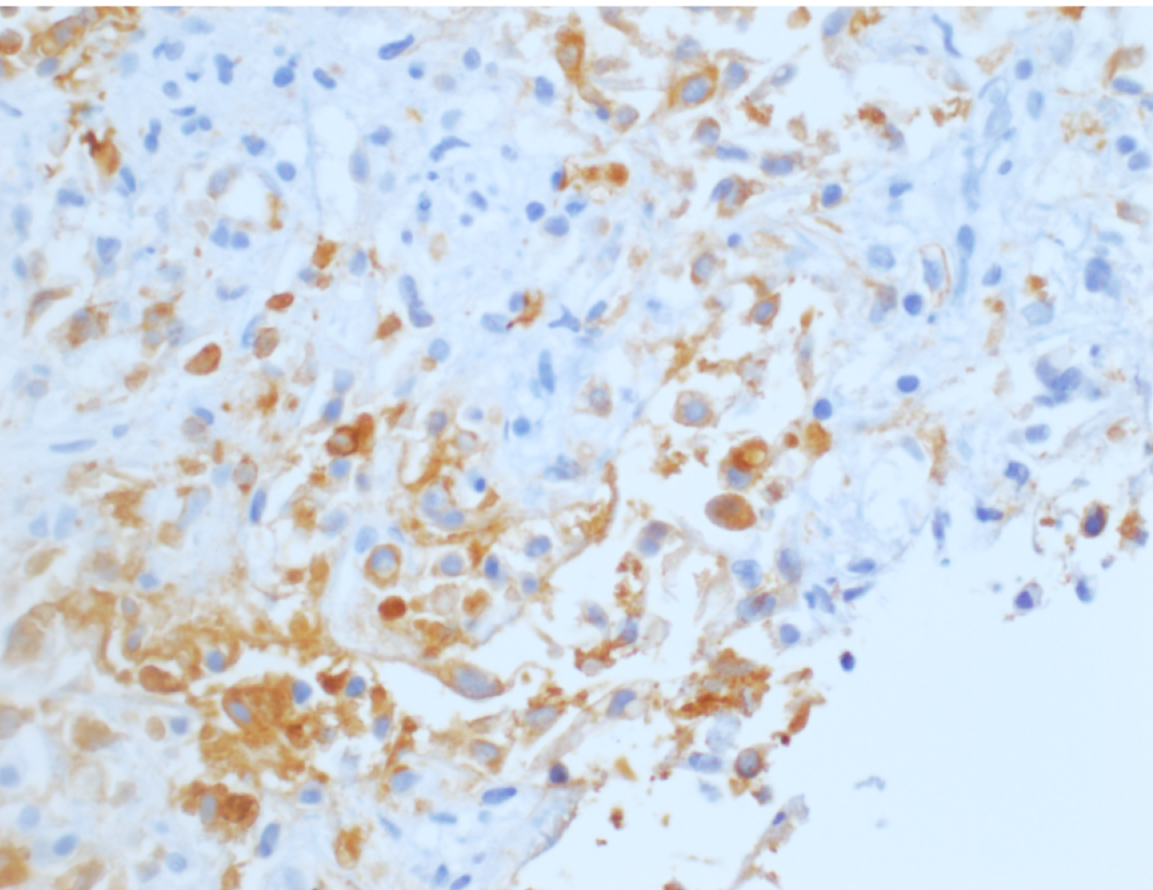

At low power, the liver core shows irregular angulated glands and single cells in a background of abundant desmoplastic stroma. (Figure 1 and 2). At high power the cells display varying degrees of cytologic atypia (Figure 3), consistent with a moderate to poorly differentiated adenocarcinoma. Immunohistochemical stains for CK7 (Figure 4) and CK19 (Figure 5) are positive. Immunohistochemical stains for Glypican-3, Arginase-1, CK20, GATA3, PAX-8 and CDX-2 are negative. In the clinical context of a single central intrahepatic lesion with absence of lesions in the rest of the body, the histologic findings are compatible with intrahepatic cholangiocarcinoma.

Figure 4: CK7 immunostain showing cells with strong positivity

Figure 5: Immunostaining for CK19 showing strong diffuse positivity

• Cytokeratin stains show considerable overlap between hepatocellular and cholangiocarcinoma; CAM5.2 (CK8/18) is positive in both intrahepatic cholangiocarcinomas as well as HCCs however HCCs would be negative for other keratins. CK7 (90%) and CK19 (80 to 90%) are positive in most cholangiocarcinomas and CK20 can be positive in peripherally located cholangiocarcinomas.